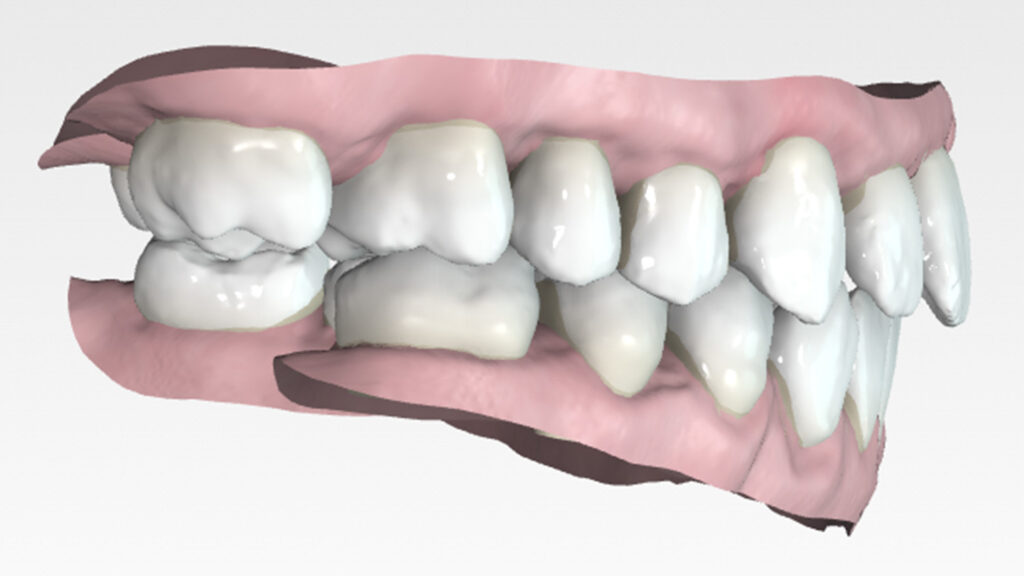

Once the transverse discrepancy was corrected, treatment continued with Spark Aligners to address the vertical plane. The planned vertical correction involved extruding the upper anterior teeth, with 1.7 mm of extrusion in the upper arch, and 1.5 mm in the lower arch using attachments. To assist in bite closure, turbo bites were employed to intrude the mandibular molars.

As shown in the accompanying images, the planned vertical correction was fully achieved. At this stage, provisional composite veneers were placed from canine to canine in the upper arch to enhance the patient’s aesthetics and compensate for Bolton’s discrepancy.

For sagittal correction, a new set of aligners made from Trugen XR™ material was fabricated. The corono-distal tipping of the premolars in the fourth quadrant was corrected using intermaxillary elastics.

Ultimately, we successfully corrected the crossbite, open bite, and Class III canine relationship. The patient rehabilitated tooth #26 with an on lay and tooth #47 with an implant, resulting in a stable occlusion. Post-treatment retention involved a fixed retainer in the lower arch and removable retainers for both upper and lower arches to maintain the treatment results.